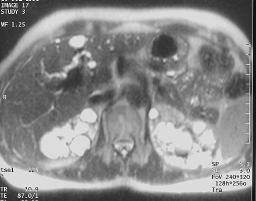

Ce patient est connu

pour être porteur d'une polykystose hépato-rénale.

En bili I.R.M. il existe un kyste du cholédoque associé à

des voie biliaires très irrégulières dans la région

péri hilaire. Les voies biliaires périphériques sont

considérées comme normales.